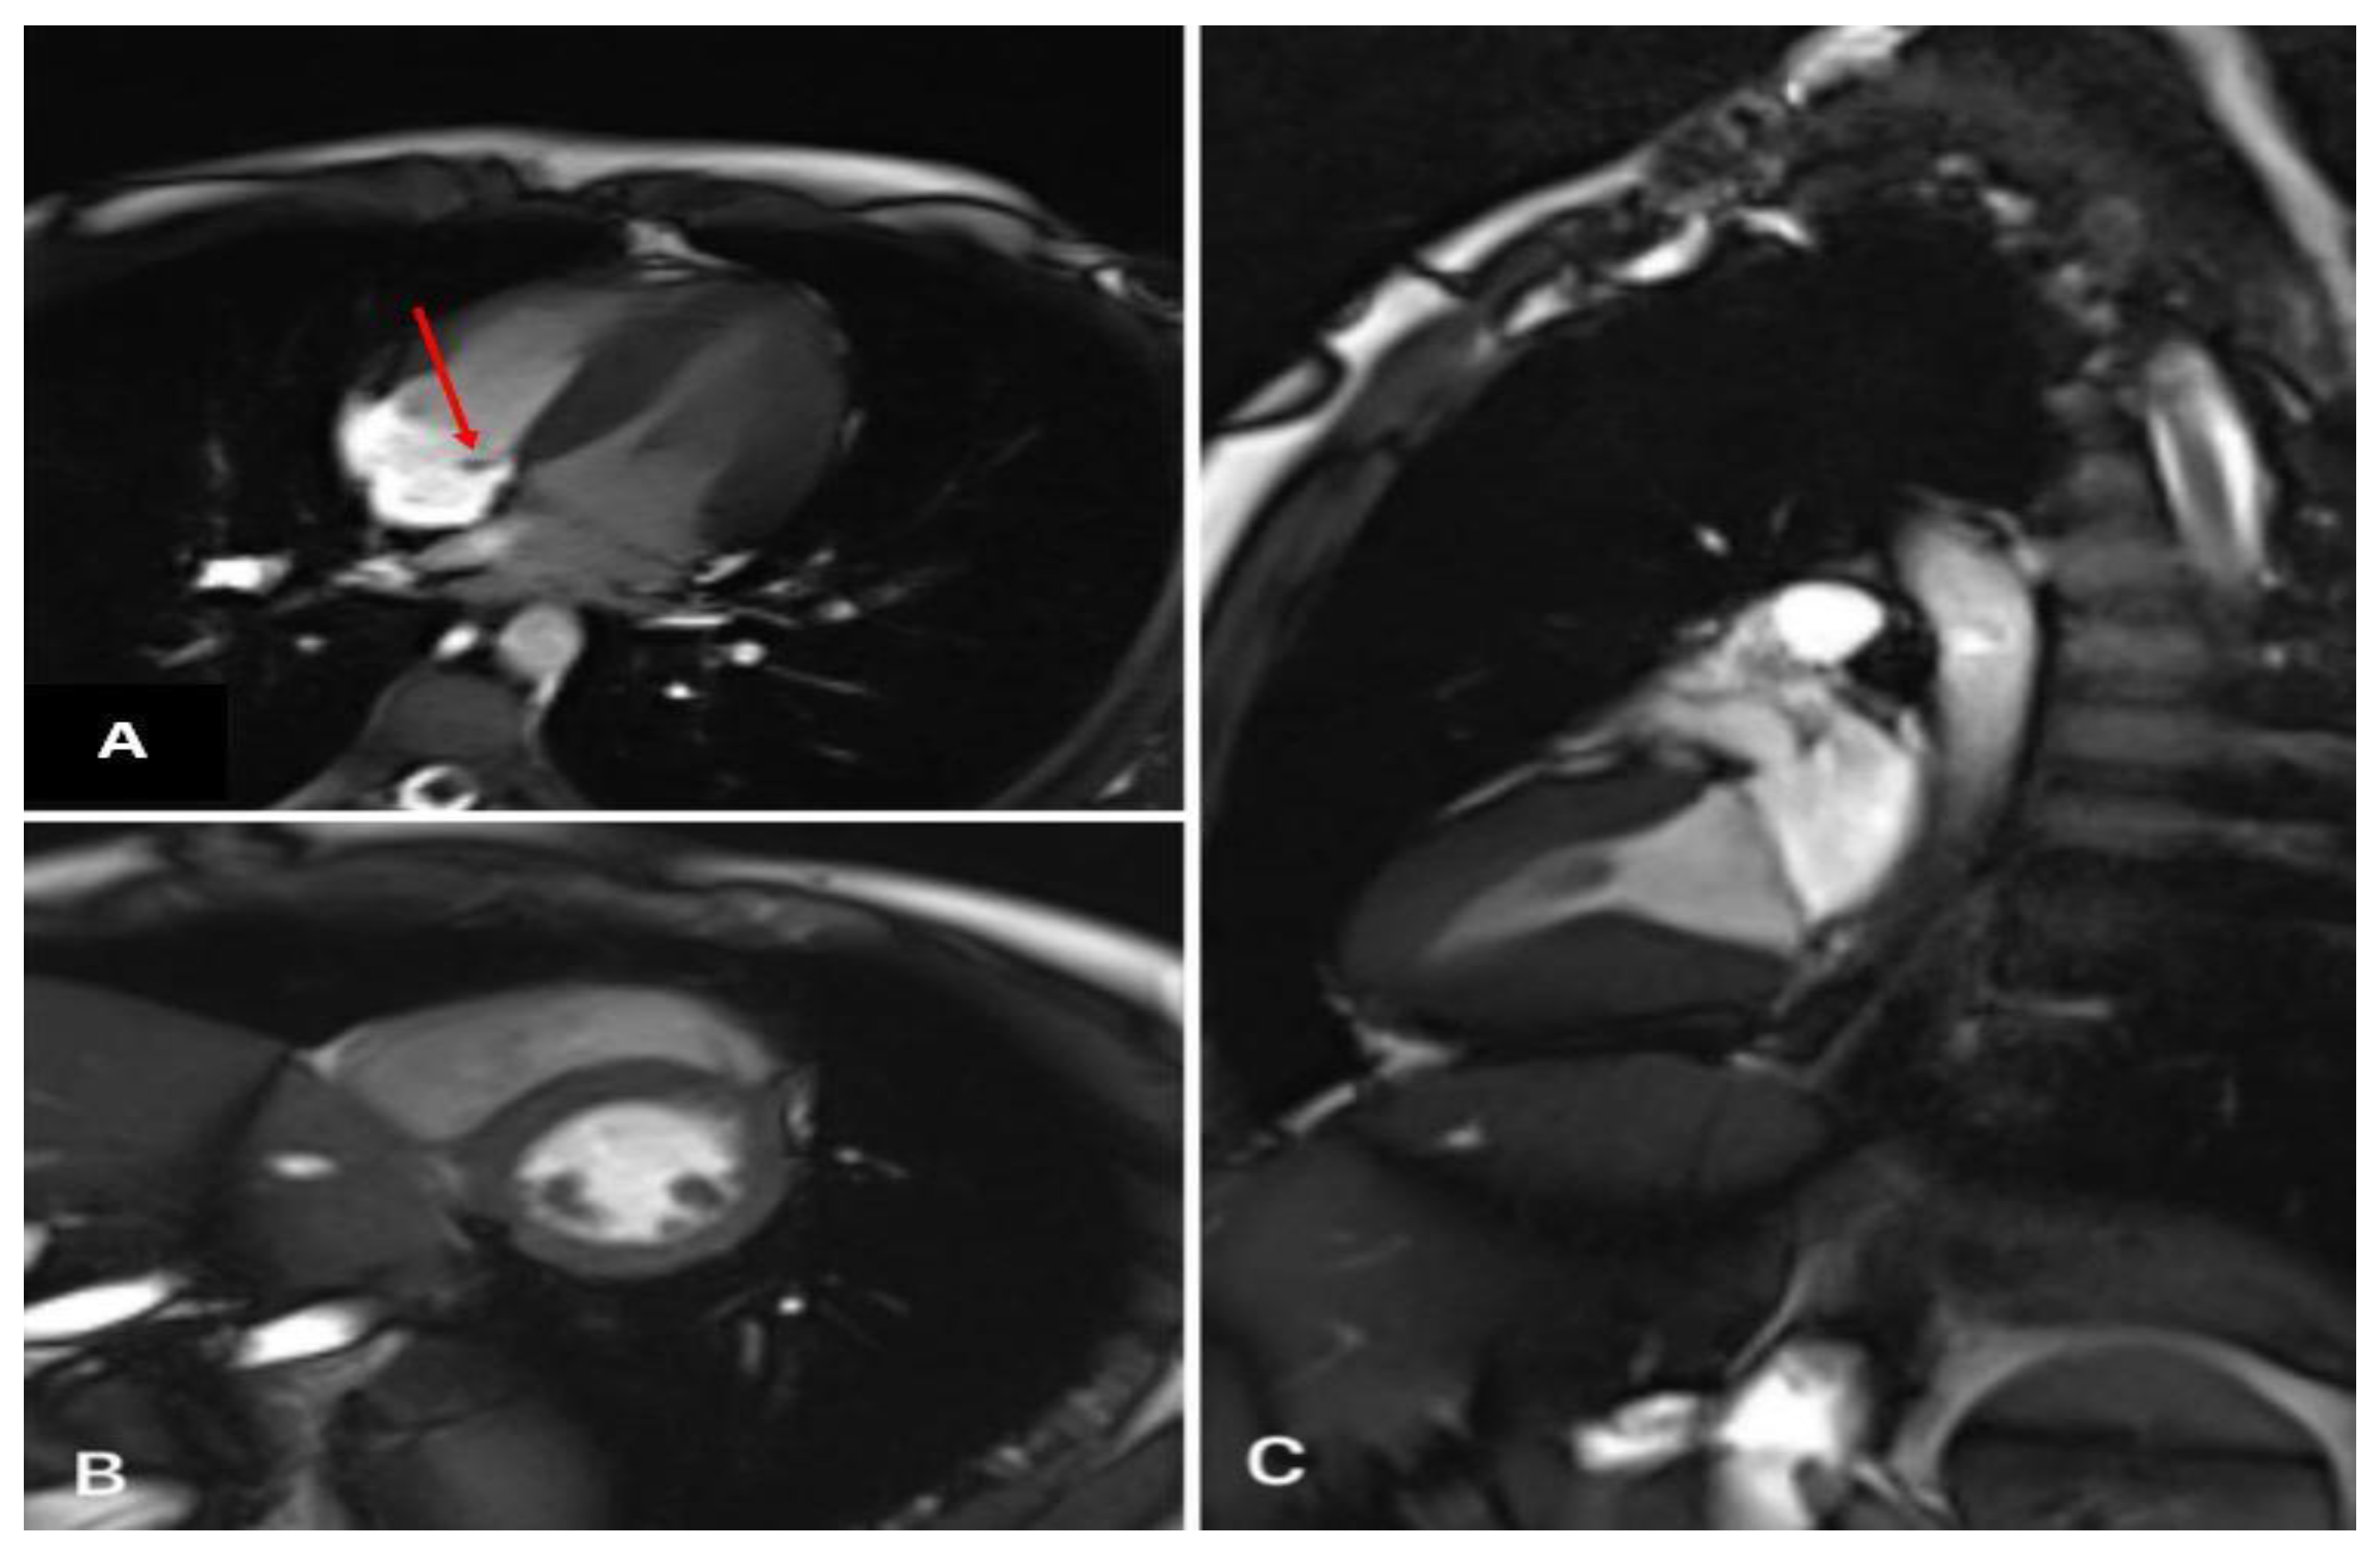

2. Case 1

2.1. Examination Data

2.2. Substantiation of Diagnosis

3. Case 2